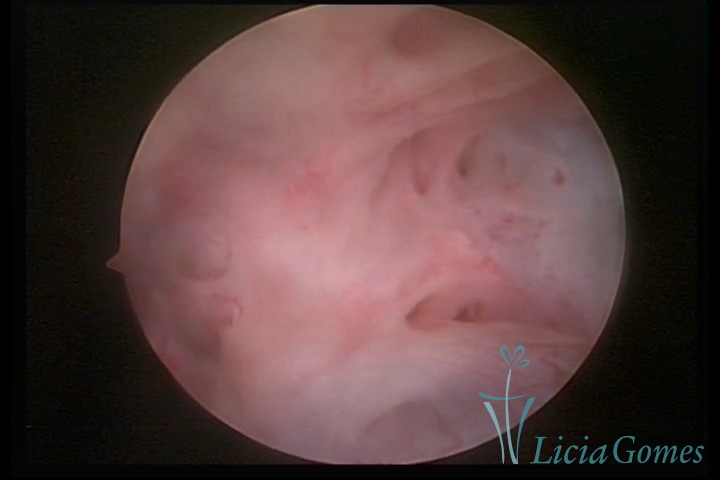

Primeira porção ou setor proximal ou setor inferior:

Durante a fase proliferativa, encontramos muco claro e cristalino pouco aderente à óptica. As criptas e as papilas apresentam-se um pouco edemaciadas e vascularizadas, micro vesicular, lembrando cachos de uva.